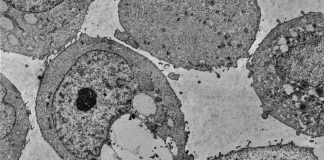

خانه برچسبها هر ۴ هفته تاخیر در شناسایی سرطان تا ۲۰ درصد میزان مرگ‌و‌میر را افزایش می‌دهد

Tag: هر ۴ هفته تاخیر در شناسایی سرطان تا ۲۰ درصد میزان مرگ‌و‌میر را افزایش می‌دهد